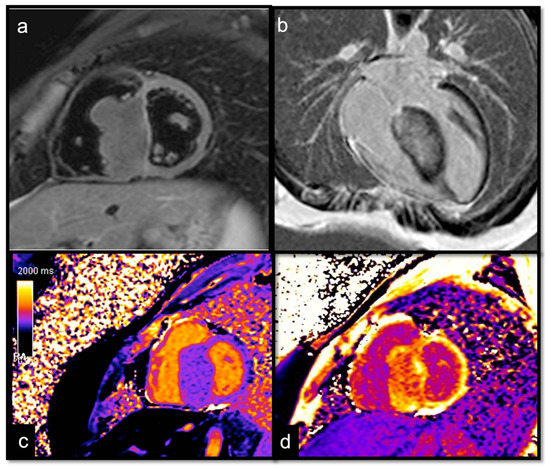

7.2.6. T1 and T2 Mapping

- Short T1/short T2 (as compared with the myocardium) for calcifications

- Short T1/long T2 for melanoma or lipomas and lipomatosis [64]

- Long T1/long T2 for most tumors, whether benign or malignant, with different degrees in particular for the T1 (close to the myocardium for rhabdomyoma, long or very long for myxomas [65] and fibroelastomas)

- T1 mapping allows for highlighting the difference between recent (<1 week) and old thrombi (>1 month), as recent thrombi have a significantly shorter T1.